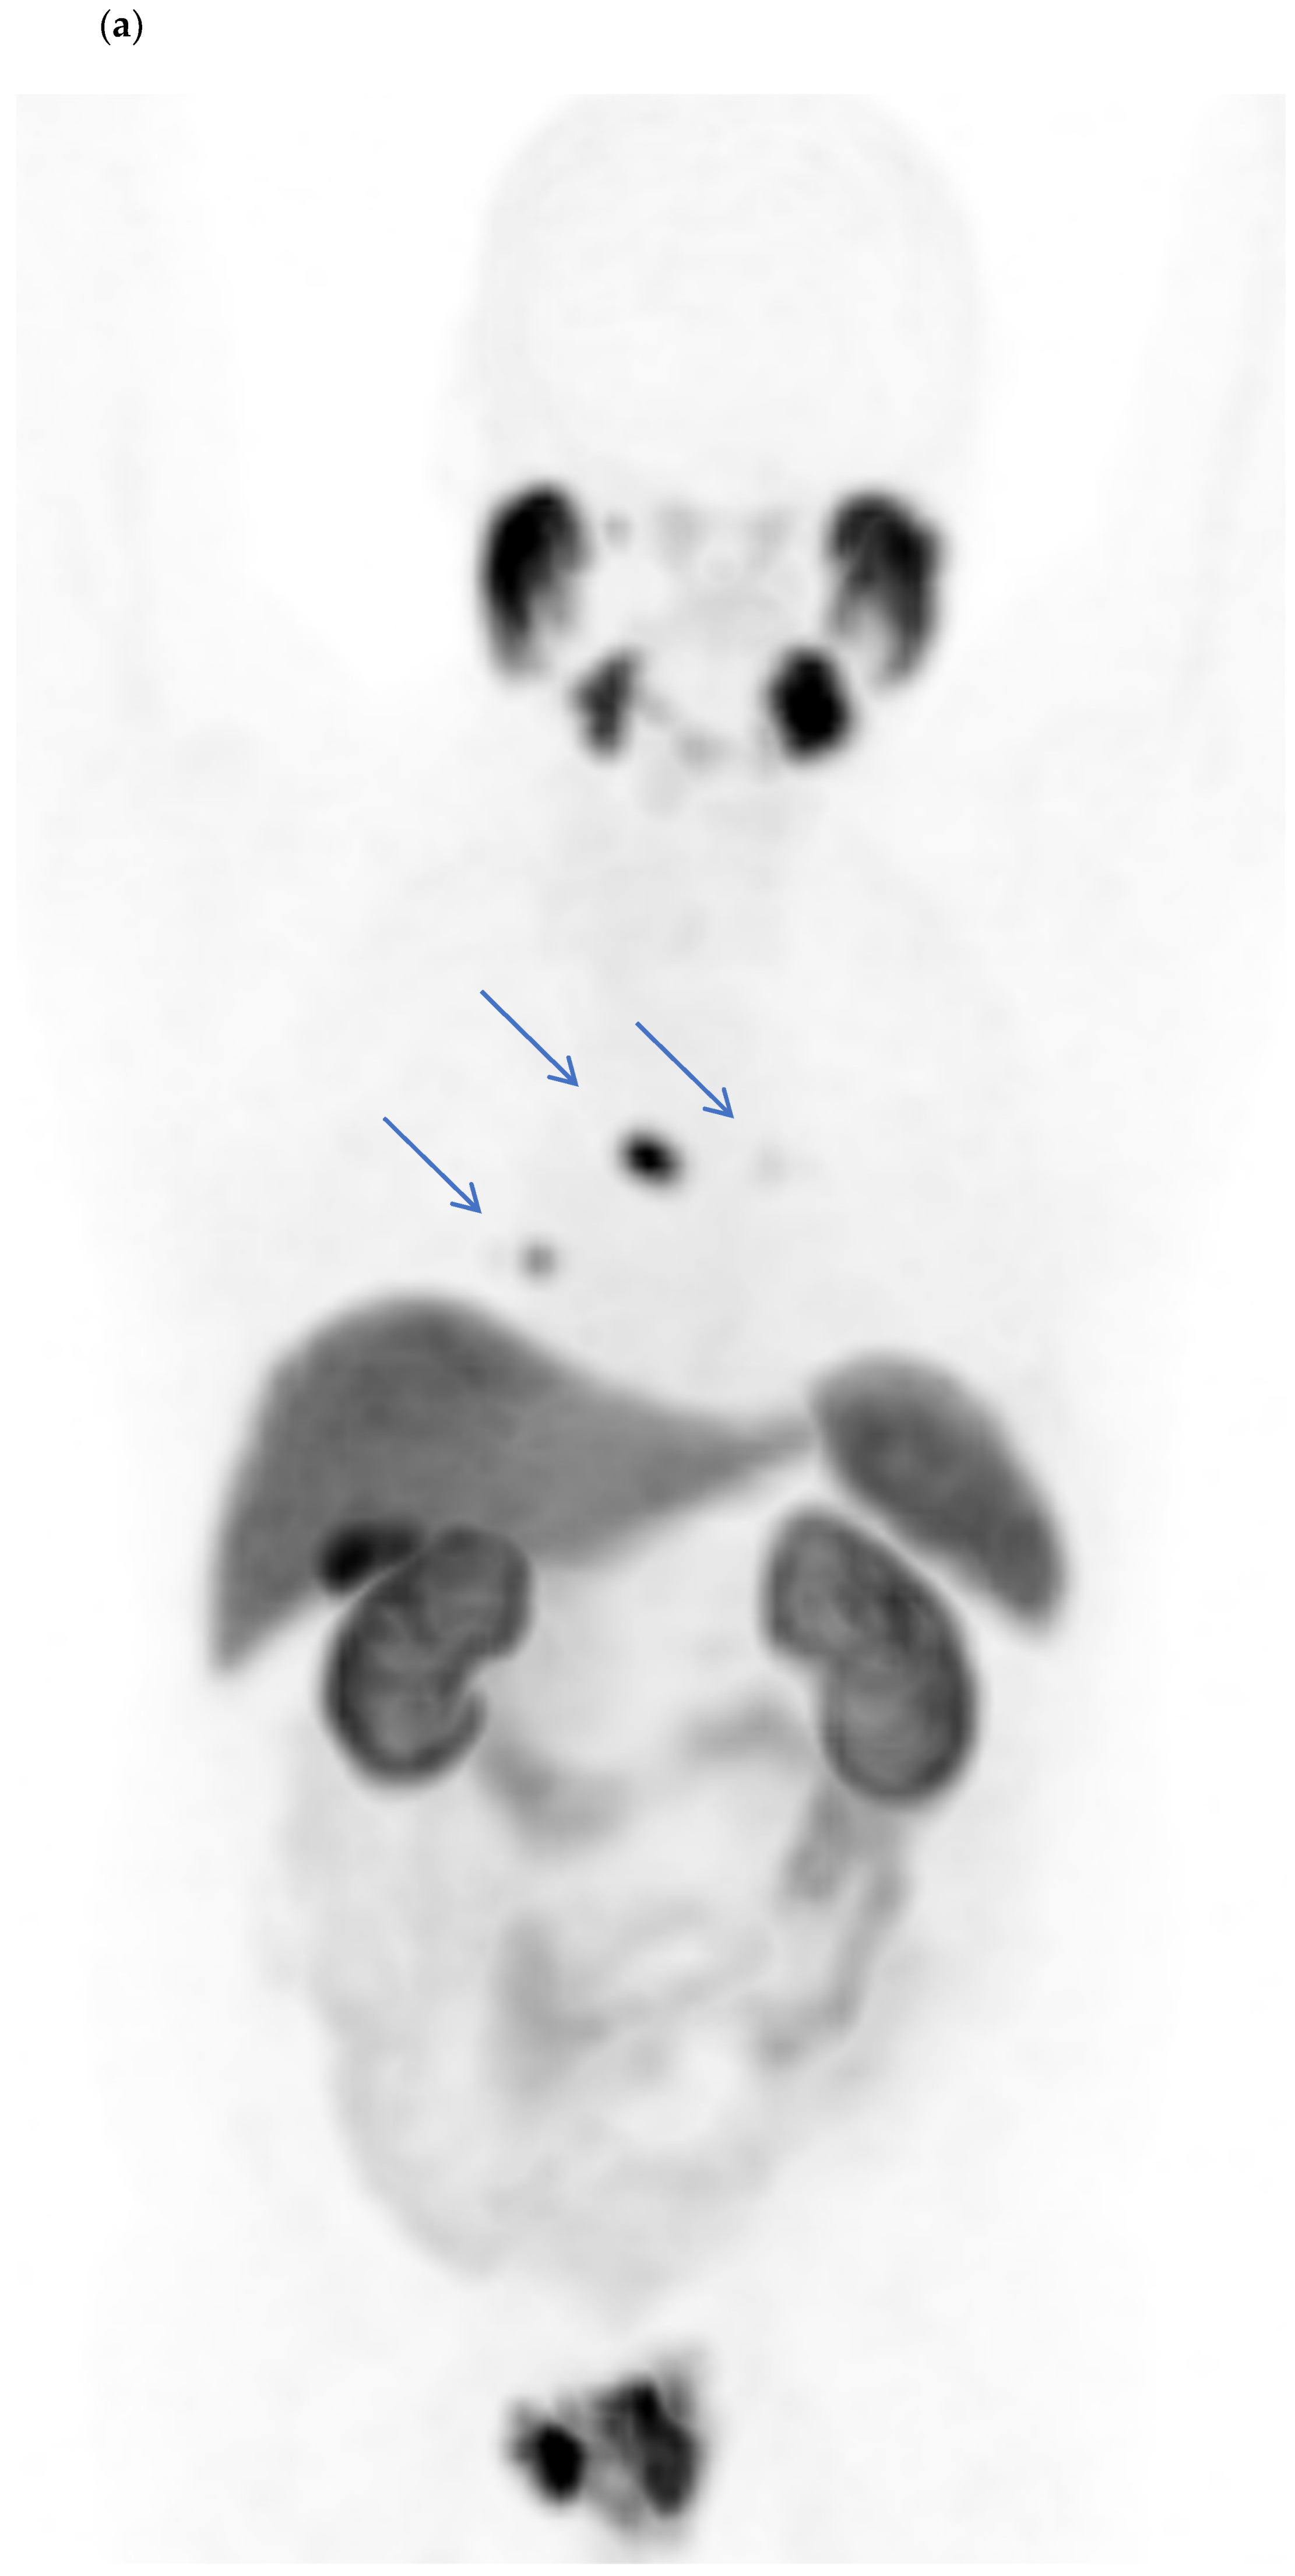

3. Results